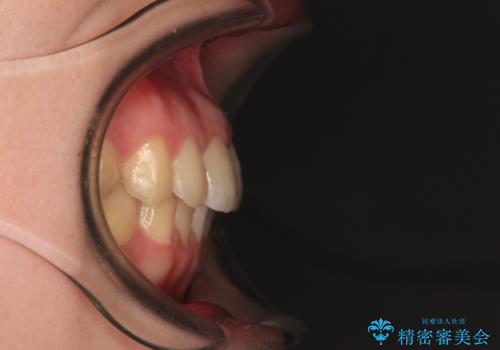

デコボコ歯列をきれいに インビザラインによる矯正治療

- 上下歯列全体のデコボコを気にして来院された患者様です。

主に下顎歯列全体の後方移動とIPR(歯と歯の間を削る)によってデコボコが解消するように設計し、インビザラインにより治療を行うこととしました。

1年半程度で終了するのではないかと予想しましたが、途中1年以上の来院がなく、トータルで3年の時間がかかってしまいました。

前歯のデコボコはより改善することが望ましい状態でしたが、患者様の希望により終了することとなりました。